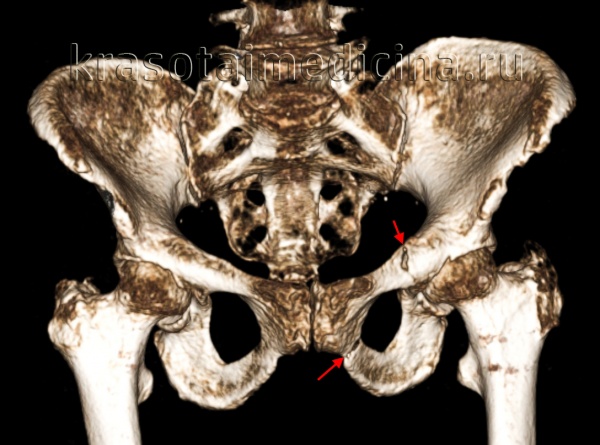

(Слева) КТ, 3D реконструкция подвздошной проекции Жюде: определяется изолированный перелом крыла подвздошной кости (Дювернье) вследствие удара о дерево при катании на лыжах. Несмотря на распространение перелома в соседнюю губу вертлужной впадины, повреждение сустава отсутствует.

• Изолированный перелом крыла подвздошной кости:

о Обычно крупный костный осколок с минимальным смещением

о Подвздошно-седалищная и подвздошно-лобковая линии не повреждены

о Для исключения поражения вертлужной впадины может быть выполнена КТ